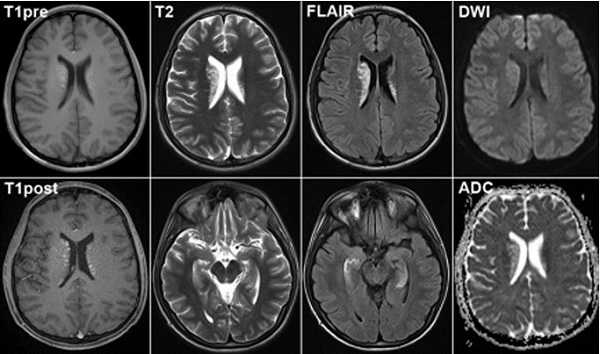

Серия снимков МРТ при подозрении на инсульт

Картина развития ишемического инсульта на МРТ (Т1- и Т2-взвешенные изображения)

В острейшем периоде (первые 6 часов) проводят диффузно-взвешенную (ДВ) МРТ. Полученные снимки отражают патологические изменения мозгового вещества через 5 минут после появления признаков инсульта. ДВ-изображения помогают определить область поражения, показывают отек тканей вокруг очага, смещение церебральных структур.

Острый период (1-7 день) характеризуется появлением четко ограниченных светлых участков на МРТ в Т2-взвешенном режиме. На Т1 ВИ очаги некроза имеют гипоинтенсивный сигнал.

Головной мозг на МРТ при разных режимах сканирования